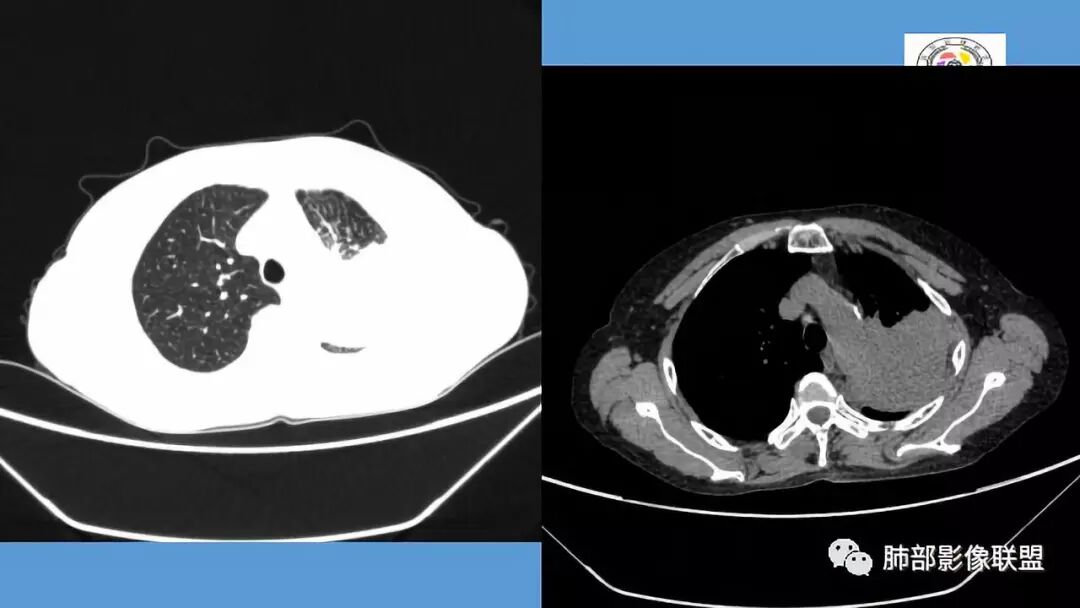

左肺病变支气管有狭窄后扩张,有部分钙化,符合结核,但叶间裂有膨隆,支气管有受压变窄表现,部分病灶内有血管,不能排除腺癌的可能,所以考虑肺结核合并腺癌可能

中年女性,慢性咳嗽,咳痰病史4个月,左肺上叶可见一团块状密度增高影,边界清,未跨叶裂,边缘有收缩有膨隆,周边可见结节影及树芽,周边部分小叶间隔增厚,内部可见点状坏死及血管包埋,有支气管充气征,部分支气管扩张,考虑淋巴瘤可能性大,鉴别结核

中年女性,咳嗽咳痰4月,加重半月。偶发热,肿瘤指标升高。病变主要位于左肺上叶后部,实变,病灶大部边缘平直、局部膨隆,邻近叶间裂局部向后膨隆,病变密度整体较均匀,见小斑片状低密度区及点状钙化影;左肺上叶舌段支气管可疑截断,病灶内支气管走形迂曲变形、不规则狭窄扩张、部分支气管内粘液栓形成,可见局部扩张支气管似小空洞相连,病灶内血管走形自然;糊墙。病灶前缘小叶间隔增厚,平滑;左肺下叶支气管管壁增厚,见部分树芽征及腺泡结节,边缘不清。纵膈及双肺门部分淋巴结钙化,隆突下淋巴结增大;未见胸腔积液。1.左肺上叶病灶倾向于恶性肿瘤,腺癌可能,排除粘液腺癌;2.左肺下叶少许炎症;

晨读:左肺上叶实变,边缘不整,部分膨隆,其内支气管有狭窄有扩张,周围小叶间隔增厚,左肺下叶背段可见气腔结节,树芽征,边缘模糊,肺门及纵膈淋巴结钙化,考虑结核。鉴别肺炎型肺癌。

左上肺片状高密度影,其内有充气支气管征,血管造影征,叶间裂明显膨隆,支持粘液腺癌,鉴别于淋巴瘤、结核